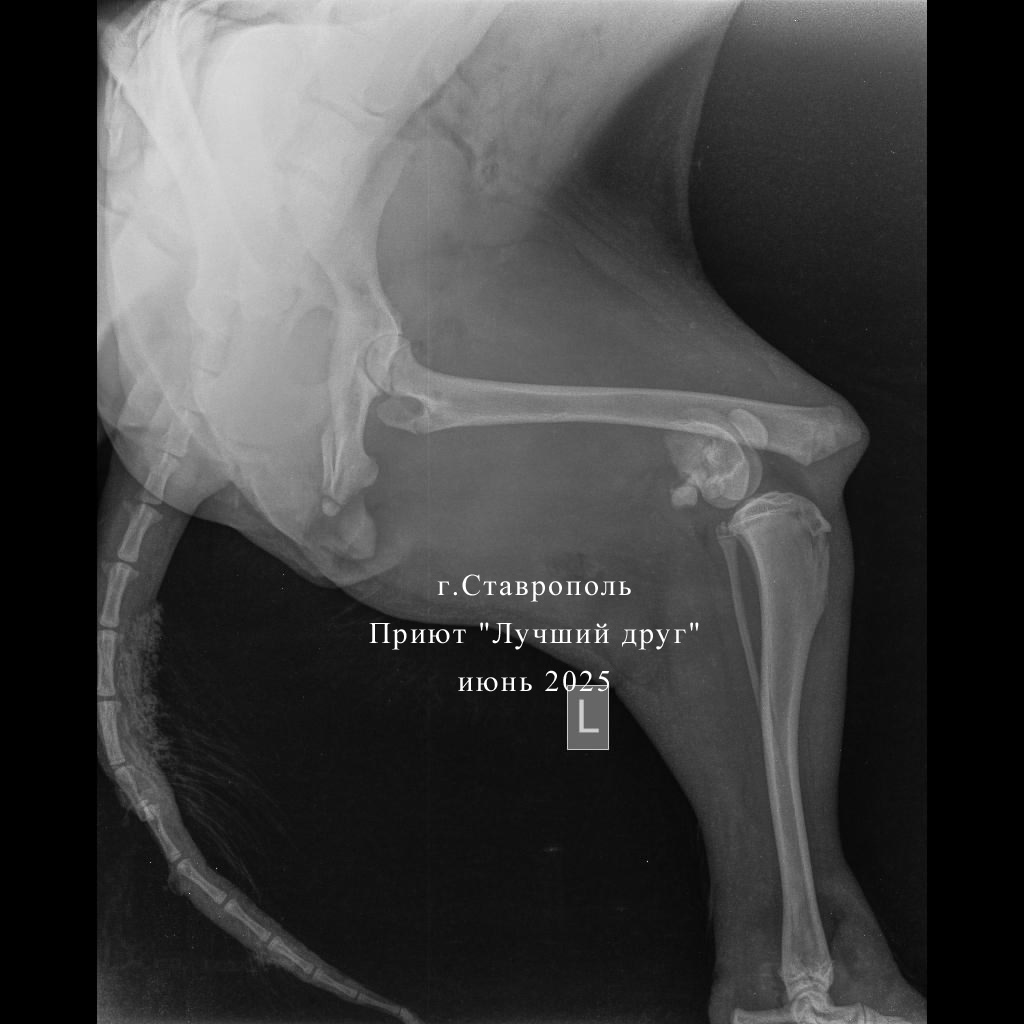

Читая истории спасения собак, поневоле задумываешься, насколько повезло животному, что кто-то его нашел вовремя и смог оказать помощь. Заре не повезло. Она три дня после ДТП валялась в кустах в беспомощном состоянии. И когда ее все-таки привезли в клинику к множественным травмам и переломам уже добавились некрозы, нагноения. Поэтому в клинике сначала провели экстренные мероприятия: обработали и максимально зачистили раны и ампутировали сгнивший хвост. И только после курса антибиотиков, несмотря на то, что по общему анализу крови анемия, взялись оперировать переломы, ждать дольше нельзя, собака рискует остаться инвалидом.

Читая истории спасения собак, поневоле задумываешься, насколько повезло животному, что кто-то его нашел вовремя и смог оказать помощь. Заре не повезло. Она три дня после ДТП валялась в кустах в беспомощном состоянии. И когда ее все-таки привезли в клинику к множественным травмам и переломам уже добавились некрозы, нагноения.

Поэтому в клинике сначала провели экстренные мероприятия: обработали и максимально зачистили раны и ампутировали сгнивший хвост. И только после курса антибиотиков, несмотря на то, что по общему анализу крови анемия, взялись оперировать переломы, ждать дольше нельзя, собака рискует остаться инвалидом.

Вчера, 17 июня, Зарю прооперировали, в выписке много медицинских терминов, но если перевести на общепонятный язык - собрали сломанные кости задних лап и было это очень непросто. Сейчас Заря отошла от наркоза и остается под наблюдением врачей.